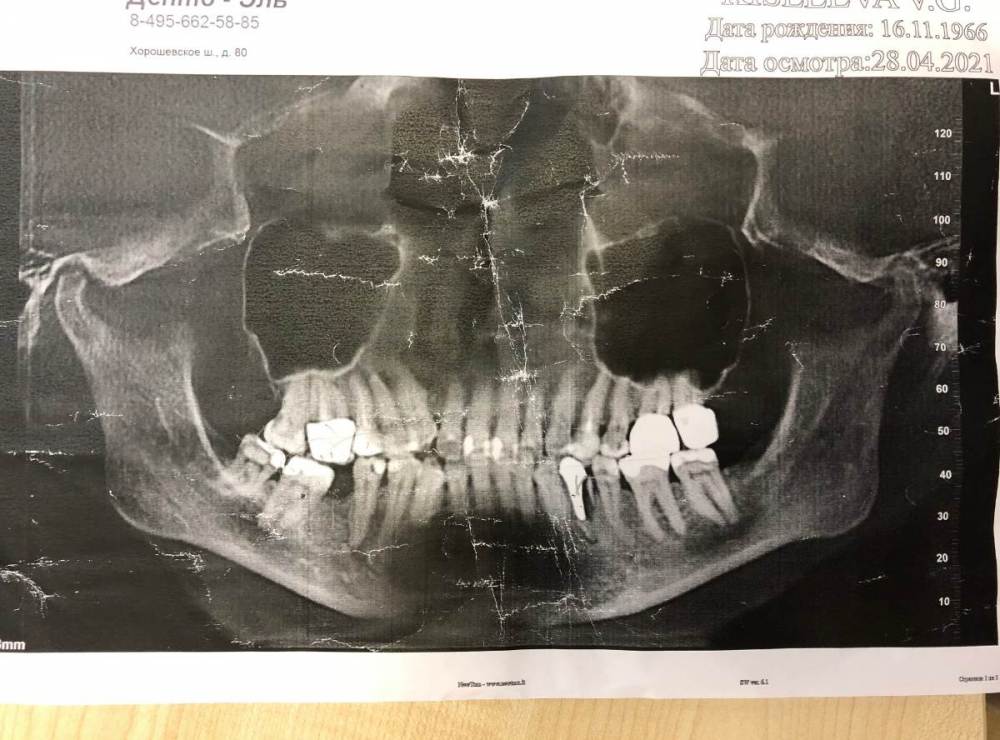

1. Срочно нужно убирать штифт из корня 34 зуба, который он расколол и похоже там воспаление. Здесь понятно, что будет имплант с коронкой. Но в одном месте говорят, что поставят имплант одномоментно с удалением, как то купируют воспаление и подсыпят костной ткани ... и всё будет хорошо ..., в другом, говорят, что нужно удалить, вылечить воспаление,  и только потом заново сверлить и ставить.   Вопрос: как лучше?

30 лет назад мне удалили 46-й и за это время никто не предложил мне туда что-нибудь вставить ... естественно, за это время 47 и 48 сдвинулись и легли на бок, сократив место под 46-й .... но честно, говоря, меня эта дырка не беспокоила, жевала и жую нормально, сустав не болит, но правильной окклюзии с этой стороны , естественно нет, поэтому и коронку на 16 зуб сделали огромную, но всё равно смыкаемость плохая ... и мне сейчас говорят, что рецессия десны на верхних у меня началась  именно из-за отсутствия 46. Такое может быть ?

ВАРИАНТ 1 - 48 зуб УДАЛИТЬ, поставить брекеты/элайнеры, подвинуть 47 и потом на место 46 имплант ... заодно брекетами исправить и все остальные ... 12 , 13 у меня не в ряду и нижние клычки выпирают ... НО, мне в этом году 55 лет !!!, какие брекеты ??? это ж расшатывание зубов и мучения минимум на 3 года .... а сделать зубы ровными - несбывшаяся мечта всей жизни ... вот и что делать ? на брекеты, пока не могу решиться, может вы настроите ...???

Правда  ортодонт сказала, что с имплантом в 34 , она  зубы на нижней челюсти двигать не сможет ... то есть вначале 34 нужно удалить, года 2-3 проходить с брекетами/элайнерами,  только потом поставить в 34 имплат и коронку.   Это на самом деле только так работает ?

ВАРИАНТ 2- с брекетами не связываться  и решить все  коронками.   Между 47 и 45 мост с имитацией 46 зуба ... 13 зуб УДАЛИТЬ, вроде как он сильно вверх и обточить для коронки нельзя ( но жалко, он у меня живой и без пломб) и далее имплат,  на 12 - винир или коронку, на 14, 15 тоже коронки, на них сильная рецессия десны и цвет совсем потемнел. Нижние клыки выровнять коронками или не трогать ???. В 11,21,22 просто поменять пломбы и подреставрировать нижний край.

Вот мои фото, очень жду вашего совета.

IMG_0001.jpg